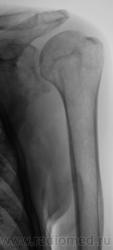

Пациент направлен хирургом на рентгенографию плечевого сустава. Травма, вроде-бы была. Хирург, не мудрствуя, направил пациента на рентгенографию. Пациент предъявляет жалобы на боли в области плечевого сустава, руку поднять не может. Врача-рентгенолога, на момент исследования в рентгеновском кабинете не было.

Но, я неоднократно повторяю, что работаю с очень хорошими лаборантами, и они прекрасно понимают, да и убедились, что если написано - рентгенография голеностопного сустава, то зачастую "написанное" не есть "то, что надо". Так и в данном случае лаборанты "захватили побольше", и дай бог, им здоровья и всего самого наилучшего.

Снимок "без обрезания" - ниже. Врача-рентгенолога в кабинете не было, лаборанты, оценив его, начали "пытать" пациента. Оказалось, что флюорографию органов грудной полости, этот пациент, "проходил" лет 5 тому. Ну, и лаборанты приступили к стандартному исследованию органов грудной полости.